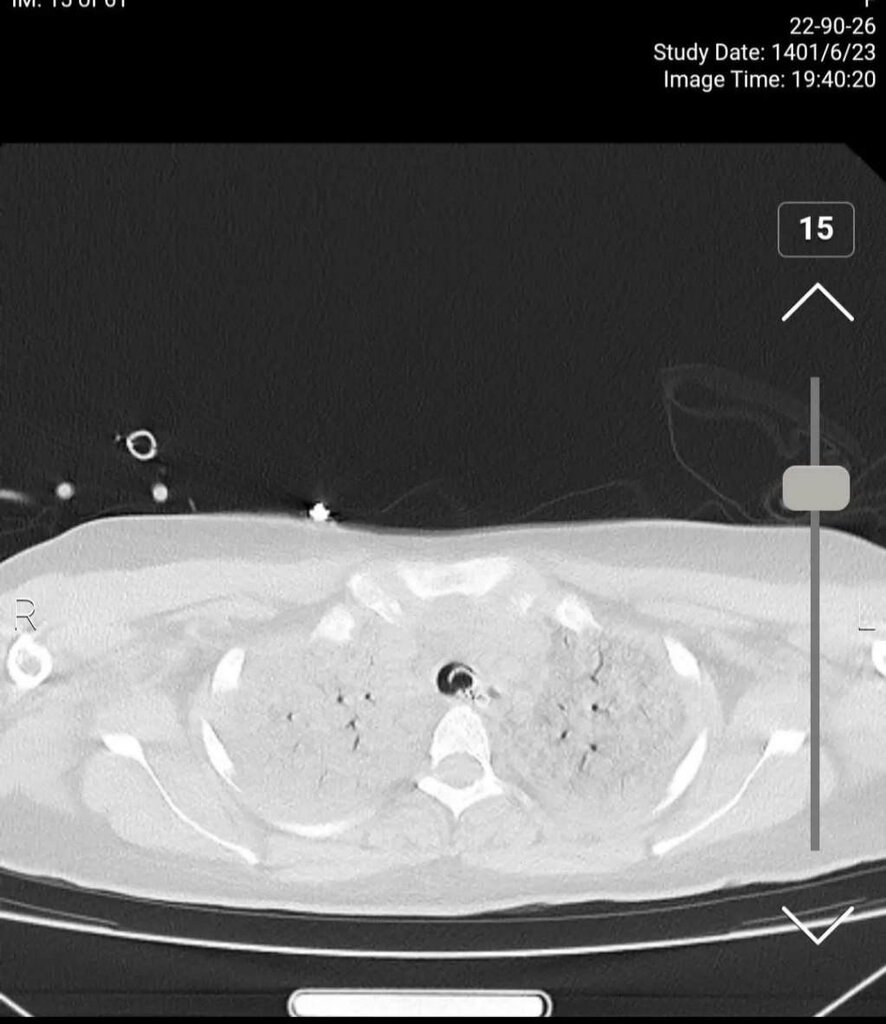

به گزارش همشهری آنلاین، صبح امروز شبکه اینترنشنال وابسته به عربستان سعودی عکسی از سیتی اسکن مرحوم مهسا امینی منتشر کرد و مدعی شد که «سیتی اسکن مهسا نشانگر شکستگی جمجمه، خونریزی و ادم مغزی است».

با اینکه در ابتدا تصور می شد این تصاویر به مانند بسیاری از اخبار این رسانه سعودی جعلی باشد اما پیگیری ها از مراجع ذیربط نشان داد تصاویر سیتی اسکن منتشر شده مربوط به مرحوم مهسا امینی است.

برای بررسی علمی این موضوع با تعدادی از پزشکان مغز و اعصاب و رادیولوژیست گفتوگو کردیم تا به صورت علمی این موضوع را بررسی کنیم. این متخصصان معتقدند بررسیهای سی تی اسکن بیمارستان نشان میدهد هیچ شواهدی از ضربه به سر و خونریزی در این تصاویر به چشم نمیخورد.

یک متخصص جراحی مغز و اعصاب گفت: بررسیها نشان میدهد که بیمار در گذشته جراحی در ناحیه سر انجام داده است اما براساس شواهد موجود از روی سیتیاسکن نمیتوان فهمید که جراحی دقیقاً مربوط به چند سال قبل است. همچنین شواهد کرانیتومی فرونتوتمپورال قبلی همراه با آتروفی مختصر عضلانی و تغییرات بافت نرم در محل جراحی بیمار مشهود است.

یکی دیگر از پزشکان مغز و اعصاب نیز جراحی تومور بیمار را تایید میکند. به گفته این متخصص مغز و اعصاب متاسفانه برخی از افراد با دیدن تصاویر ناقص سی تی اسکن درفضای مجازی اقدام به اعلام نظر کردهاند اما واقعیت این است که در تصاویر کامل اثری از شکستگی نیست و این رسانه سعودی تصاویر را از زاویهای منتشر کرده است که شکستگی به نظر برسد.

برای بررسی دقیقتر موضوع سراغ پزشکی دیگری رفتیم. متخصص مغز و اعصاب دیگر میگوید: بیمار در گذشته جراحی سر انجام داده و بخشی از تومور در ناحیه سوپراسلار باقی مانده است. بررسی بیشتر سی تی اسکن بیانگر این است که با توجه به نوع جراحی انجام شده در این ناحیه وقوع دیابت بیمزه در بیمار دور از انتظار نیست و با توجه به آتروفی لوب فرونتال راست احتمال صرع را نمیتوان برای بیمار رد کرد هرچند اساساً تشخیص صرع یا دیابت بیمزه با سیتیاسکن مقدور نیست.

برای بررسی وضعیت ریه بیمار نیز با تخصص رادیولوژی گفتوگو کردیم که وی توضیح میدهد: در سیتیاسکن ریه شواهد کانتیوژن یا له شدگی بافت ریه مشاهده میشود که پس از «سی پی آر» رخ میدهد و ممکن است در هر بیماری رخ دهد و این موضوع غیرطبیعی نیست.